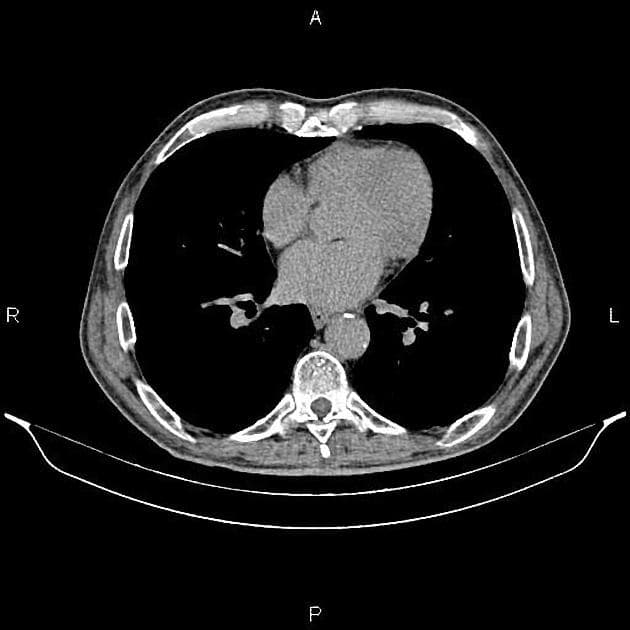

Axial renal excretory phase

CT•Axial renal excretory phase•1 / 110

- Một khối ngấm thuốc kích thước 28 x 20 x 22 mm nằm ở phần trên của hệ thống đài bể thận phải.

- Ngoài ra, thấy nhiều nang vỏ mỏng đơn thuần không ngấm thuốc ở vỏ thận hai bên, đường kính tối đa 48 mm.

- Khối u tế bào biểu mô niệu quản thận phải đã được chứng minh bằng giải phẫu bệnh, không có bệnh lý hạch vùng (regional lymphadenopathy) hay di căn rõ trên hình ảnh.

- Trên cắt lớp vi tính (CT), tổn thương thường có mật độ mô mềm với mức độ ngấm thuốc nhẹ, thường thấp hơn đáng kể so với nhu mô thận hoặc ung thư tế bào ống thận.

Ung thư tế bào biểu mô niệu quản thận khởi phát từ biểu mô chuyển tiếp của đài bể thận và được phân loại mô học là một dạng ung thư biểu mô niệu quản. Bệnh chiếm khoảng 5–10% các ung thư thận, hiếm gặp hơn nhiều so với ung thư tế bào ống thận. Trên CT có cản quang, tổn thương điển hình là khối mô mềm nhỏ trong đài bể thận với mức độ ngấm thuốc nhẹ đến trung bình. Do vị trí và đặc điểm ngấm thuốc không rõ rệt, khối u dễ bị bỏ sót, đặc biệt khi không có giãn đài bể thận. Chẩn đoán thường được nghĩ đến ở bệnh nhân tiểu máu không đau, nhất là những người có yếu tố nguy cơ như hút thuốc hoặc tiếp xúc nghề nghiệp với amin thơm. Chẩn đoán xác định cần dựa vào sinh thiết hoặc mẫu mô sau phẫu thuật. Điều trị chủ yếu là cắt thận – niệu quản toàn bộ kèm cắt vạt bàng quang, tùy theo giai đoạn bệnh và tình trạng bệnh nhân.